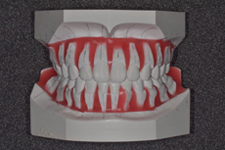

検査模型

初診時

予測模型